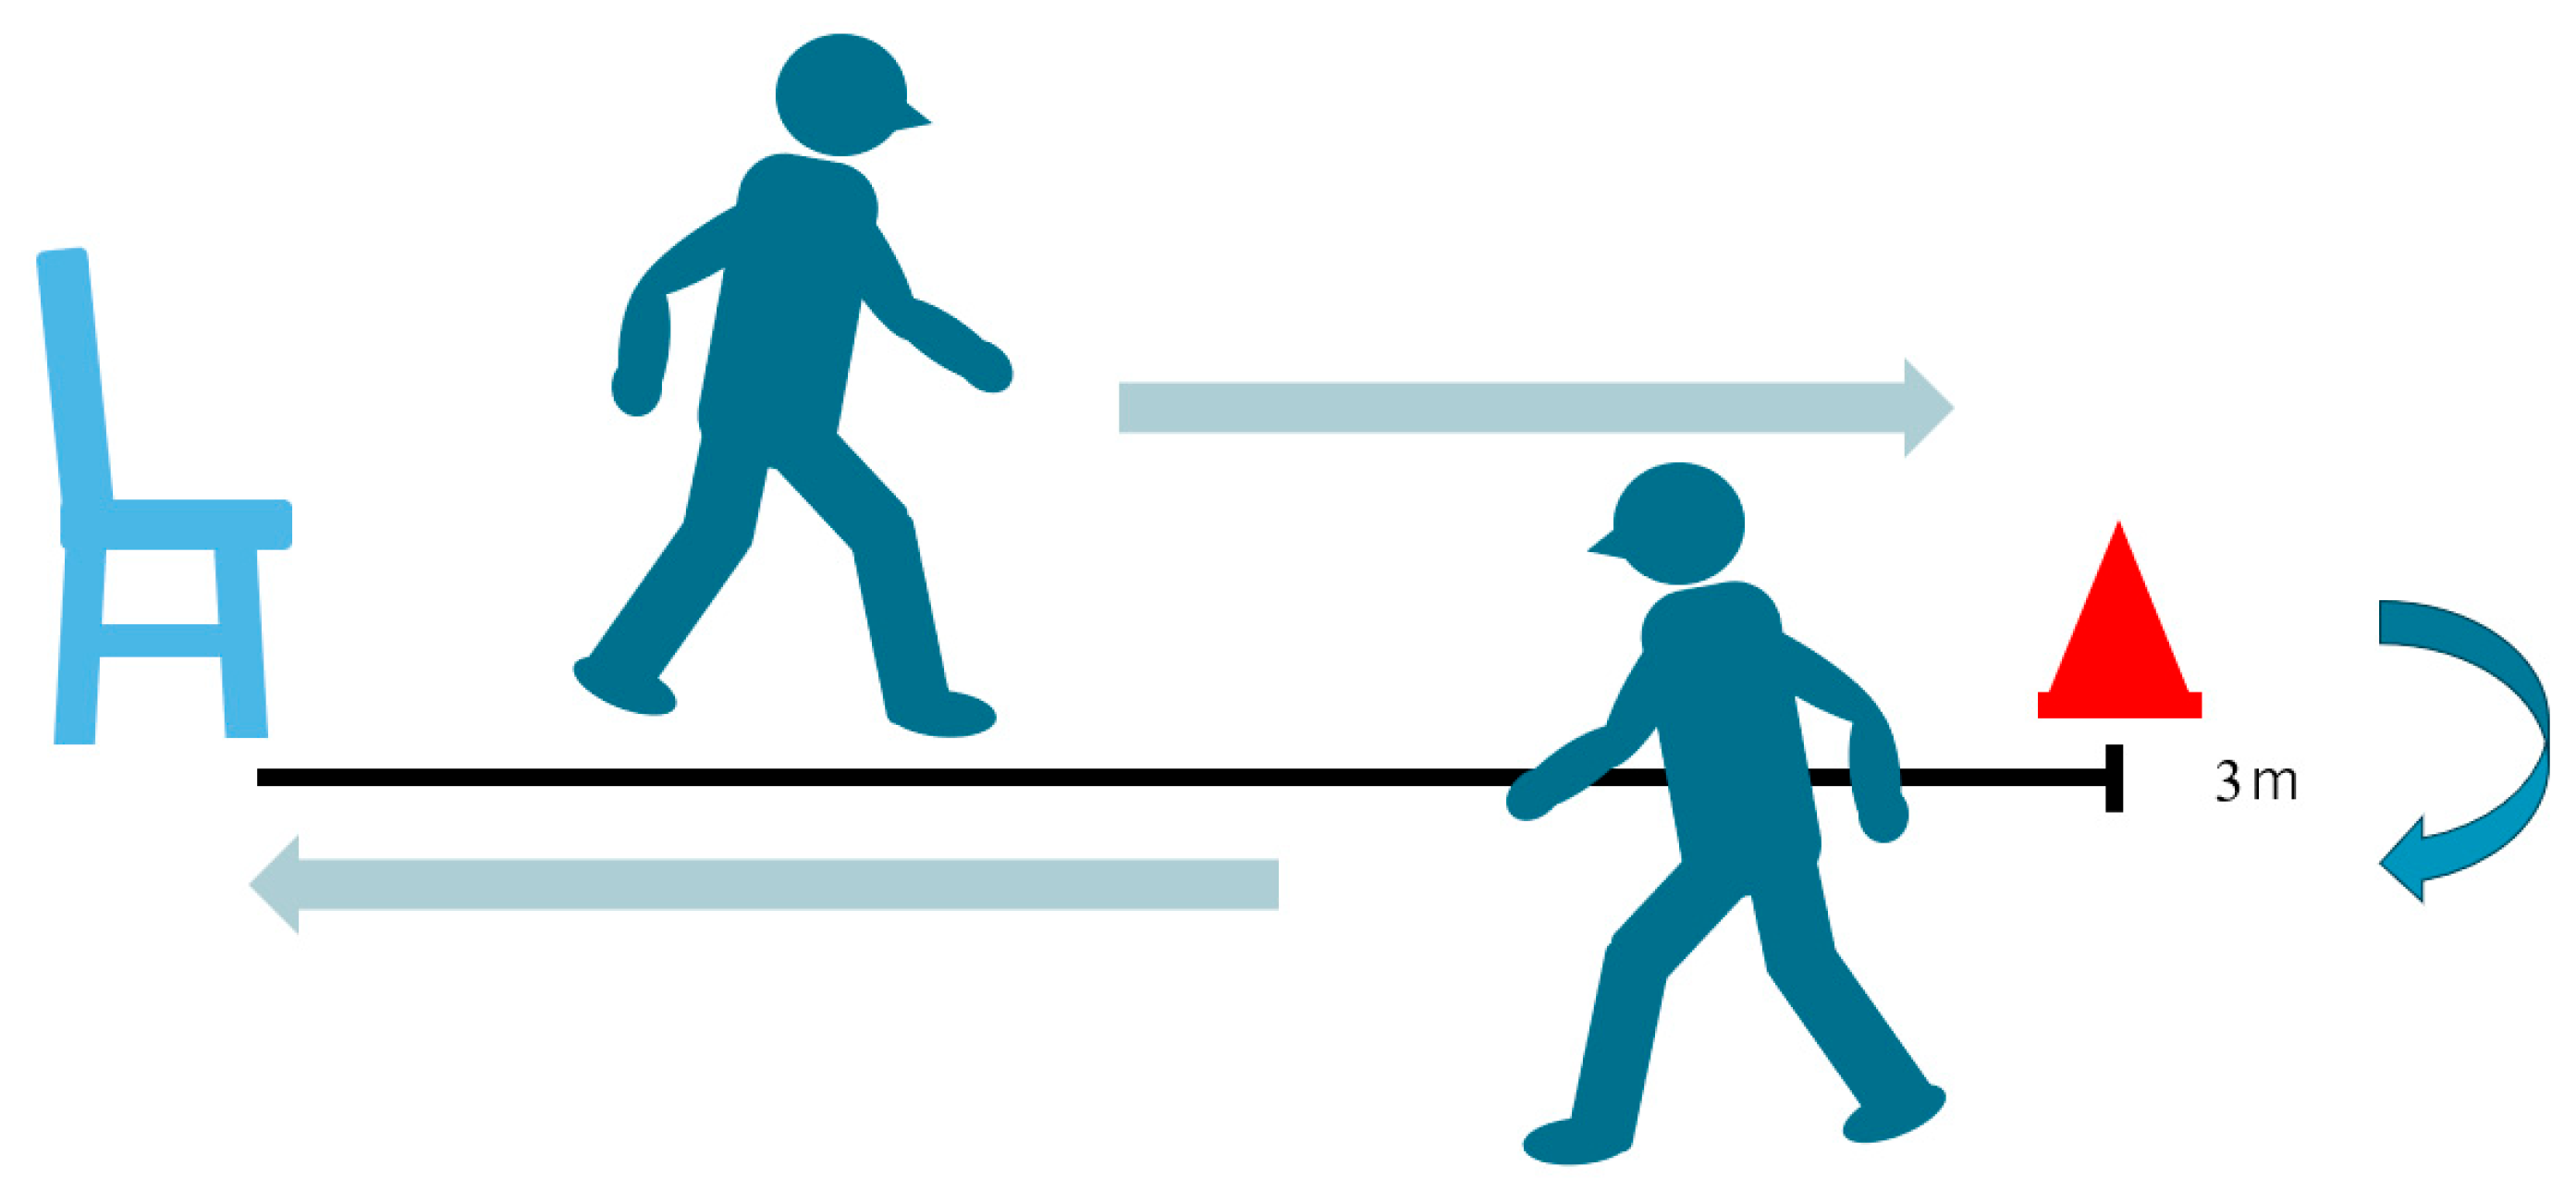

2.2. Outcome Assessment

2.2.2. Timed Up-and-Go Test (TUG)